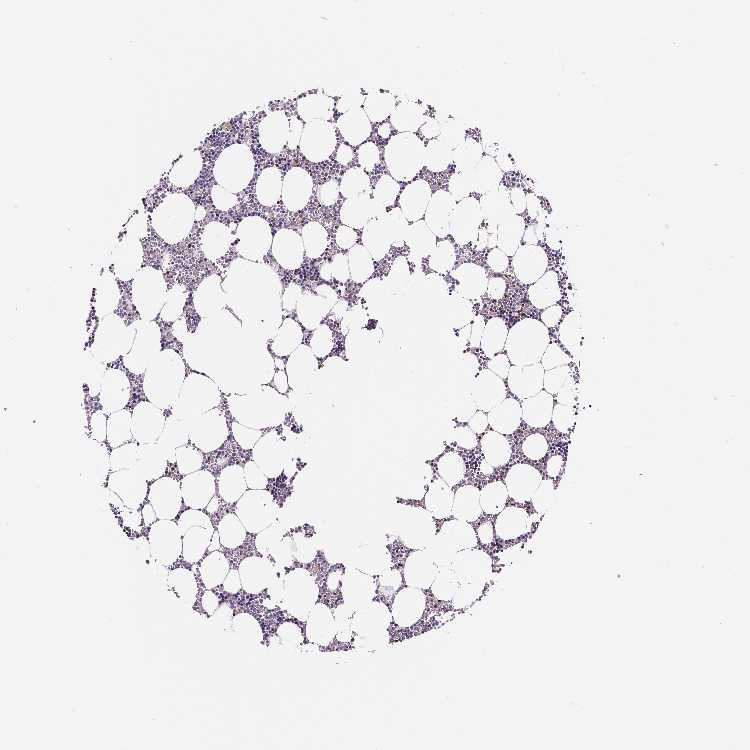

BONE MARROW - Antibody stainingi

Antibody staining in the annotated cell types in the current human tissue is reported as not detected, low, medium, or high, based on conventional immunohistochemistry profiling in selected tissues. This score is based on the combination of the staining intensity and fraction of stained cells.

Each image is clickable and will lead to virtual microscopy that enables deeper exploration of all samples and also displays staining intensity scores, fraction scores and subcellular localization as well as patient and tissue information for each sample.

Antibody HPA005533Antibody CAB068196Antibody CAB068197

Hematopoietic cells Not detectedLowNot detected